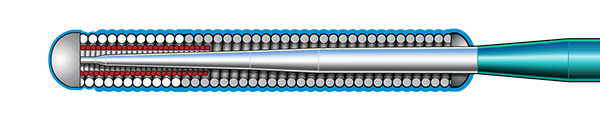

Guidewire Technology

Inner Coil Technology

The advanced design of the stainless steel core and Inner Coil Technology provides a unique combination of exceptional torqueability, rail support, and shape retention.

- Stainless steel inner coil affixed directly to the distal end of the guidewire core

- Improved durability and ease of shaping

- Exceptional torqueability without whipping

Micro EMTTM Technology

MICRO EMT exactly matches the taper of the core and coil, allowing for a lower profile and a more flexible core, leaving almost no room for the core to move within the coil, resulting in 1:1 torque.

- Entry: The smallest tip on the market (0.008”) and the long taper (6 cm) facilitate easy lesion entry in even the most complex lesions.

- Maneuverability: A flexible distal shaft enables excellent intraluminal navigation in complex lesions, with minimal perforation risk.

- Torque: With exactly matched tapers, the core and coil move as one, eliminating whip and empowering precise steerability.